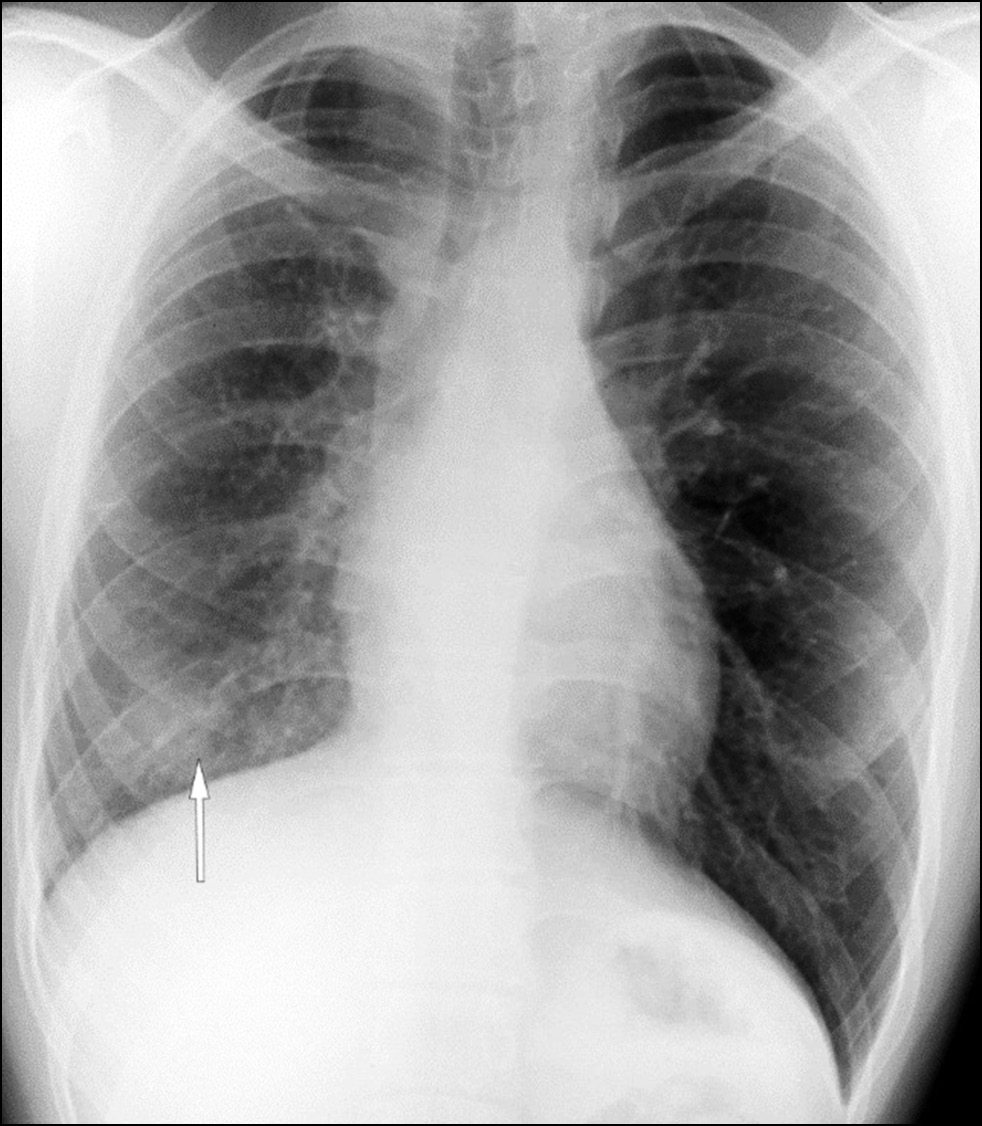

Unilateral pulmonary vein atresia: Difficulties of radiological diagnosis

Abstract

Pulmonary vein atresia is a rare congenital abnormality that could manifest in isolation or in association with other congenital abnormalities in the cardiovascular system such as pulmonary vein hypoplasia. Pulmonary vein atresia leads to changes in cardiovascular functioning. This abnormality is often diagnosed in children with recurrent pneumonia and hemoptysis. In adulthood, pulmonary vein atresia is much less common, with clinical symptoms such as dyspnea during physical exercises and hemoptysis. However, some patients are asymptomatic. Owing to the nonspecific imaging findings, lung parenchymal changes are often misdiagnosed as another lung disease, including inflammatory genesis disease. In this article, a case of a young man with asymptomatic unilateral pulmonary vein atresia combined with pulmonary artery hypoplasia and interstitial lung changes in a lung with hypoplasia was presented. These pathologies were first identified in a 21-year-old patient by contrast-enhanced computed tomography.